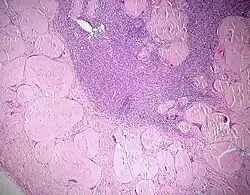

- TOUTON-Riesenzelle - Schaumzellen, bei denen um eine kleine schaumfreie Insel mehrere Kerne ringförmig angeordnet sind, Vorkommen z.B. bei juveniler Xanthogranulomatose, siehe Abb.

![]() |